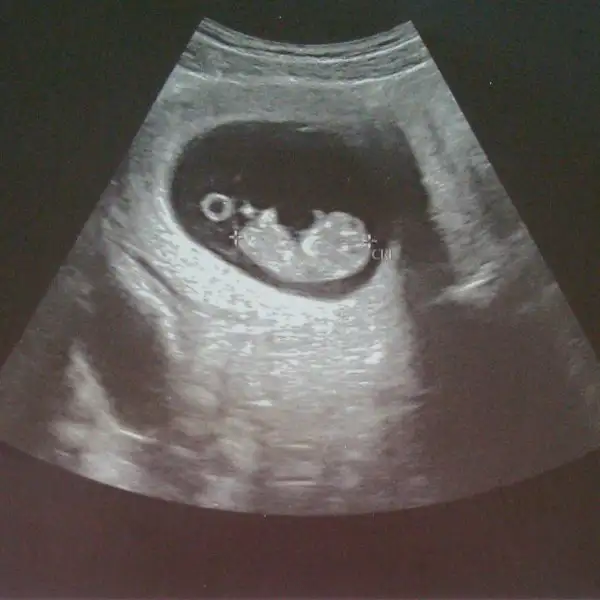

Hayırlısı olsun canım. Inşallah sonuç güzel çıkar. Okudun mu bilmiyorum bizim de ense kalınlığı 1.2 cıktı sağlıklı bir bebeğe benziyor dedi. 12+6 cıktı 6.5cm olmuş boyu. 1 kilo almışım bende. Cinsiyete de bu kez kız gibi duruyor 1 ay sonra net söylerim dedi :)Slm canim.geldim eve.biraz uyudum simdi kalktim.

Ins güzel ve risksiz cikar canim.Okudum canim.bizim bebisler ayni gidiyor gibi.yalniz benimki biraz minik.galiba iyi beslenemiyorum ondan.Hayırlısı olsun canım. Inşallah sonuç güzel çıkar. Okudun mu bilmiyorum bizim de ense kalınlığı 1.2 cıktı sağlıklı bir bebeğe benziyor dedi. 12+6 cıktı 6.5cm olmuş boyu. 1 kilo almışım bende. Cinsiyete de bu kez kız gibi duruyor 1 ay sonra net söylerim dedi :)

Ins güzel ve risksiz cikar canim.Okudum canim.bizim bebisler ayni gidiyor gibi.yalniz benimki biraz minik.galiba iyi beslenemiyorum ondan.

Canım o biraz da genetik benim oğlum hep 2 hafta önde giderdi. Benim eşim 1.90 boy kilo da var maşallah :) o yuzden cocuklar da babanın genetiginden önde gidior :) 1.2 yı ben sordum sağlıklı görünüyor ama kesin bişey diyemem 2li testle belli olur dedi. Ben yaptirmadim amaIns güzel ve risksiz cikar canim.Okudum canim.bizim bebisler ayni gidiyor gibi.yalniz benimki biraz minik.galiba iyi beslenemiyorum ondan.